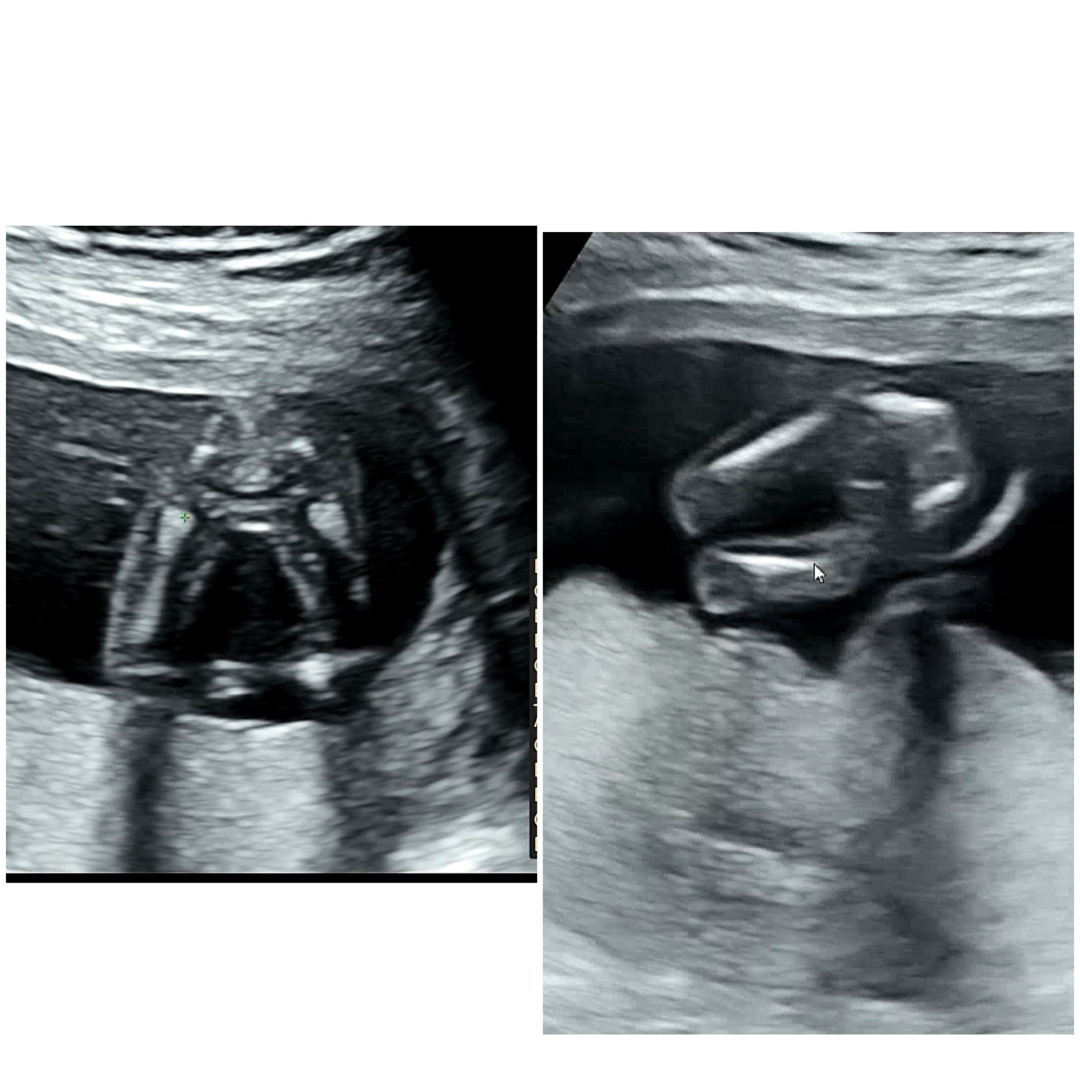

우리둥이 성별 빼박이죠??

오늘 15주 초음파 보고왔어용 딸둥이 확정이죵???